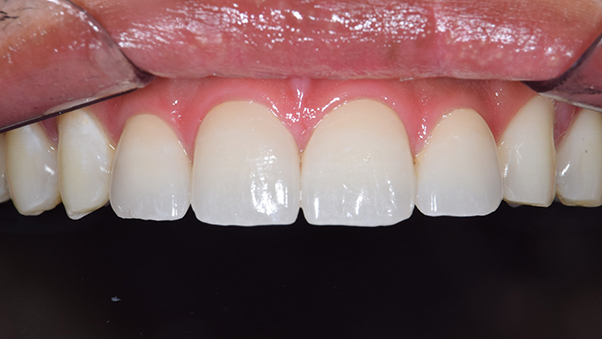

奥歯の詰め物の治療終了後

奥歯の治療が終わったところです。前歯の治療に行く前に、噛み合わせをしっかり確認します。

全ての治療終了後

前歯の治療が終わったところです。前歯は全く違和感がなく入っています。

治療後

全体の治療前後

銀歯の主張がなくなり、とても自然になりました。見た目もそうですが、雰囲気や第一印象もかなり変わりました。